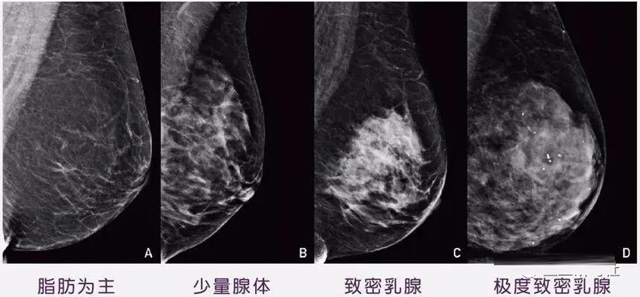

女性乳腺的自我檢查,特別是注意有小結(jié)節(jié),腫塊,乳頭有液體滲出情況,需要通過乳腺DR,X光線,磁共振等影像技術(shù)檢查。胸的大小跟乳腺癌沒多大關(guān)系,乳腺的密度大發(fā)病率高一些,胸小脂肪少致密性大。更容易乳腺癌。這個(gè)還不能通過自我檢查來確認(rèn)。致密乳腺組織看上去是白色或淺灰色需要通過乳腺X射線檢查。

乳腺X射線有輻射,40歲以下的女性沒有高危因素跟臨床特征,醫(yī)生都是不建議使用鉬靶檢查。乳腺超聲無創(chuàng)無輻射,對乳腺組織分辨率高??梢詫⑷橄倌[塊從致密型乳腺組織中輕松查出來,多普勒模式檢查乳腺及病變,超聲小于1厘米的病灶非腫塊性乳腺癌檢出率低。超聲檢查結(jié)果依賴醫(yī)生水平和經(jīng)驗(yàn),乳腺DR超聲推動(dòng)乳腺超聲圖像的標(biāo)準(zhǔn)化,提高檢查的準(zhǔn)確率。對乳腺組織內(nèi)的細(xì)小鈣化灶, 從范圍、乳腺X射線形態(tài)以及分布特點(diǎn)上進(jìn)行定性診斷。造影劑增強(qiáng)型乳腺X線攝影靜脈注射碘化造影劑結(jié)合乳房X線攝影。磁共振MRI對乳腺癌研究的深入對軟組織具有較高的分辨率等特點(diǎn),在臨床上被廣泛認(rèn)可。乳腺CT的探測器圍繞著乳房成像,無痛無擠壓,3D乳房圖像乳腺病灶的大小、數(shù)量、形狀、位置以及血管分布。一次掃描可創(chuàng)建多達(dá)兩千張投影圖像 。乳腺PET,適合普通人群和乳腺癌高危人群早期檢測,發(fā)現(xiàn)極早期微小病灶并明確定性。